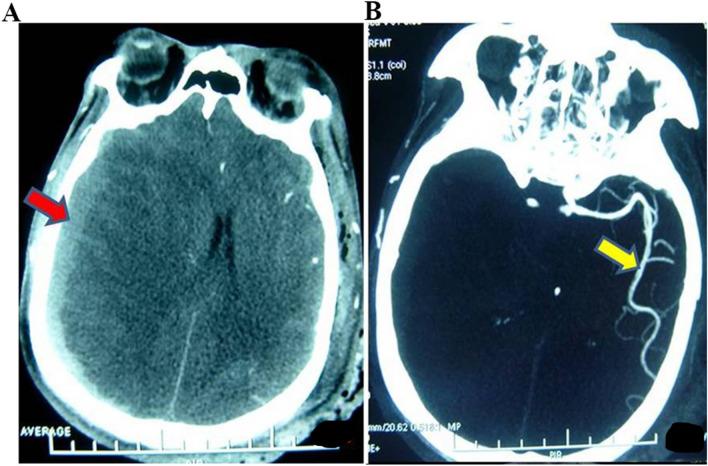

It is difficult to predict the surgical effect and outcome of severe traumatic brain injury (TBI) before surgery. This study aims to approve an evaluation method of computed tomography angiography (CTA) to predict the effect of surgery and outcome in severe TBI. Between January 2010 and January 2020, we retrospectively reviewed 358 severe TBI patients who underwent CTA at admission and reexamination. CTA data were evaluated for the presence of cerebrovascular changes, including cerebrovascular shift (CS), cerebral vasospasm (CVS), large artery occlusion (LAO), and deep venous system occlusion (DVSO). Medical records were reviewed for baseline clinical characteristics and the relationship between CTA changes and outcomes. Cerebrovascular changes were identified in 247 (69.0%) of 358 severe TBI patients; only 25 (10.12%) of them had poor outcomes, and 162 (65.6%) patients had a good recovery. Eighty-three (23.18%) patients were diagnosed with CVS, 10 (12.05%) had a good outcome, 57 (68.67%) had severe disability and 16 (19.28%) had a poor outcome. There were twenty-six (7.3%) patients who had LAO and thirty-one (8.7%) patients who had DVSO; no patients had good recovery regardless of whether they had the operation or not. Cerebrovascular injuries and changes are frequent after severe TBI and correlate closely with prognosis. CTA is an important tool in evaluating the severity, predicting the operation effect and prognosis, and guiding therapy for severe TBI. Well-designed, multicenter, randomized controlled trials are needed to evaluate the value of CTA for severe TBI in the future.